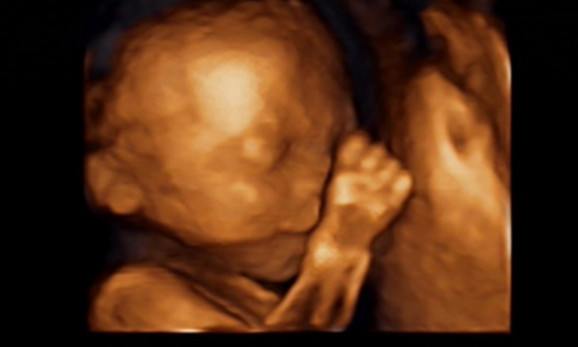

27岁的曹女士,已经怀孕六个月了。三天前,“孕味十足”的她,在丈夫的陪同下来到医院,准备进行提前预约好的四维彩超检查。但是万万没想到,检查结果让她的心情一下跌入低谷!通过影像显示,胎儿嘴唇中间竟然有一指宽的裂痕。经过医生再次仔细确认,腹中的胎儿确实患有唇腭裂,也就是“兔唇儿”。

唇腭裂患儿,是由于牙槽突间骨策划的缺失,导致上颌牙弓的完整性丧失,鼻基底部塌陷,牙槽突裂隙部恒尖牙萌出受阻。胎儿出生以后,需要通过牙槽突植骨术来完成唇部整形。手术具体怎么做,什么时候做,要做几次,这些都要根据孩子的具体病情。至于是否要生出来,这个就要由孕妇及家人自己决定。